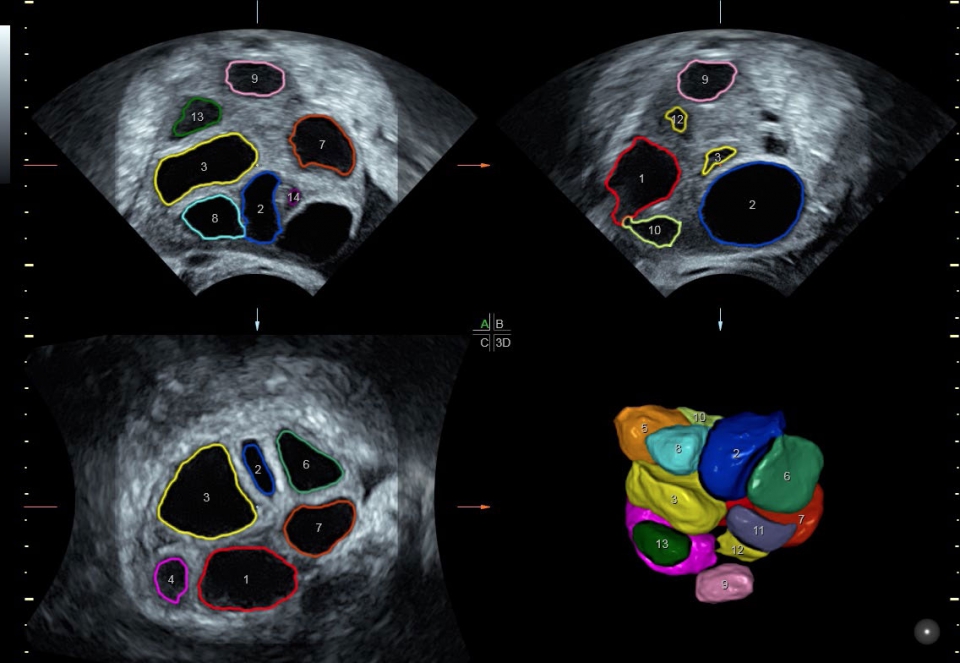

• SonoAVC (Автоматический расчет объема): Эта функция позволяет визуализировать и рассчитывать размеры и объем гипоэхогенных образований, таких как фолликулы яичника или структуры головного мозга плода. Она помогает в оценке этих образований и отслеживании их изменений в течение времени.

Да

• Расширенный программный пакет объемного контрастного изображения (VCI) для объемных датчиков